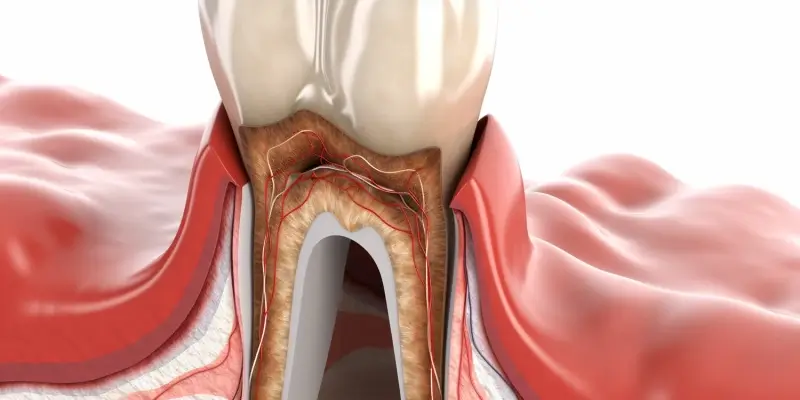

Dostępność różnych rodzajów sztucznych zębów jest szeroka i dostosowana do indywidualnych potrzeb pacjentów. Najpopularniejsze opcje to protezy całkowite i częściowe oraz implanty dentystyczne. Protezy całkowite są stosowane w przypadku braku wszystkich zębów w łuku dentystycznym i są najczęściej wykonane z akrylu lub żywic kompozytowych. Protezy częściowe natomiast są stosowane w sytuacji, gdy pacjent ma jeszcze kilka naturalnych zębów i potrzebuje uzupełnienia brakujących elementów. Implanty dentystyczne to bardziej zaawansowana opcja, która polega na wszczepieniu tytanowych śrub w kość szczęki, co zapewnia stabilność i trwałość rozwiązania. Inną możliwością są mosty protetyczne, które łączą dwa zdrowe zęby i zastępują brakujący element w łuku dentystycznym. Każdy z tych typów ma swoje zalety i wady oraz różne koszty związane z ich wykonaniem.

Protezy i implanty dentystyczne to dwie główne opcje dostępne dla osób potrzebujących uzupełnienia brakujących zębów, ale różnią się one znacznie pod względem konstrukcji, kosztów oraz trwałości. Protezy dentystyczne to ruchome lub stałe uzupełnienia, które można łatwo zdjąć i założyć. Są one zazwyczaj tańsze niż implanty i mogą być stosowane w przypadku braku wielu zębów. Jednak ich stabilność nie jest tak wysoka jak w przypadku implantów, co może prowadzić do dyskomfortu podczas jedzenia czy mówienia. Z kolei implanty dentystyczne to tytanowe śruby wszczepiane w kość szczęki, które pełnią rolę korzeni naturalnych zębów. Dzięki temu implanty są znacznie bardziej stabilne i trwałe, co pozwala na swobodne jedzenie oraz mówienie bez obaw o ich przesuwanie się. Koszt implantów jest zazwyczaj wyższy niż protez, ale ich żywotność jest znacznie dłuższa, co czyni je bardziej opłacalnym rozwiązaniem na dłuższą metę.